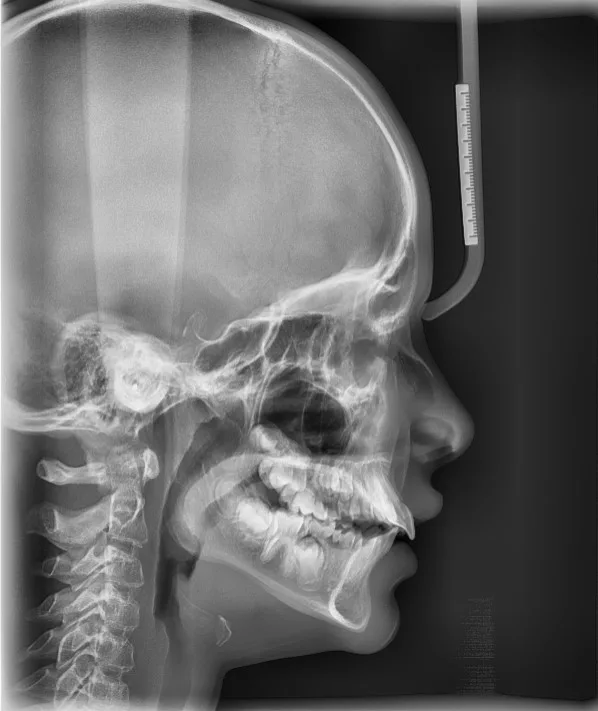

Das Wachstum ist ein wichtiger Faktor in der Behandlungsplanung bei Kindern. Insbesonders kommt es auf die Wahl des richtigen Behandlungsbeginnes, die richtige Auswahl des Behandlungsgerätes und individuelle Faktoren an.

Während Zähne sich bis ins hohe Alter bewegen lassen, ist die Beeinflussung des Knochenwachstums von Ober- und Unterkiefer nur eine begrenzte Zeit möglich. Da viele Kinder Wachstumsprobleme haben, sollte die Notwendigkeit einer Therapie einmal spätestens zur Zeit des Schneidezahnwechsels – in der Regel im Alter von sieben bis acht Jahren – und ein weiteres Mal in der zweiten Phase des Zahnwechsels – mit zehn bis elf Jahren – von einem Kieferorthopäden überprüft werden.